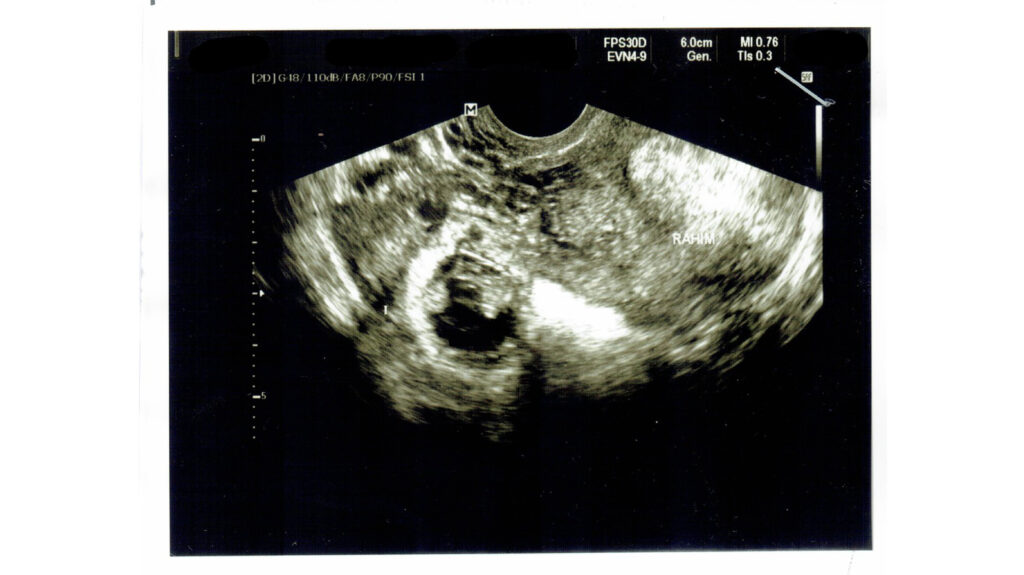

Cảnh báo: Dấu hiệu thai ngoài tử cung so với thai bình thường